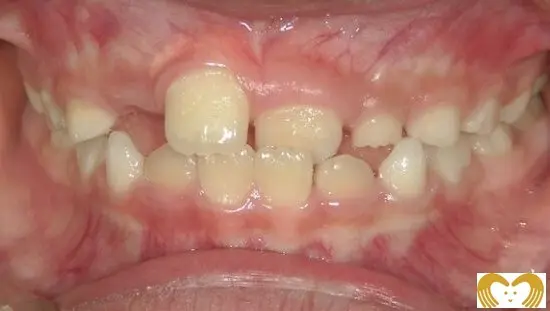

症例03:出っ歯

《Before》《After》

- 年齢:

- 8~12歳

- 性別:

- 男の子

- 治療内容:

- ネオキャップシステムによる、上顎前突(出っ歯)の治療。矯正前後のレントゲン比較から、気道(黄色矢印部分)が広くなっていることがわかります。現在は、当初見られた口呼吸も改善され、自然と鼻呼吸ができるようになりました。

- 治療回数・期間:

- 約4年間

- 治療費:

- 495,000円(税込)

- リスク:

- 取り外し可能な装置の為、治療の効果が使用頻度に左右されます。